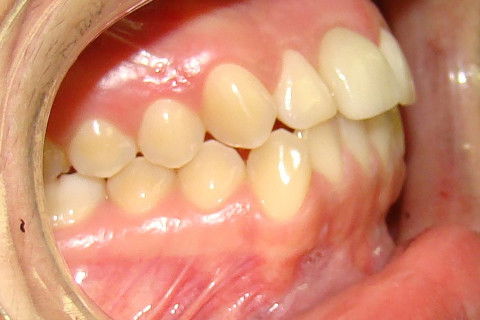

Retorno após 9 meses da colocação de coroa metalo-ceramica parafusada

Retorno após 9 meses da instalação de coroa metalo-ceramica parafusada